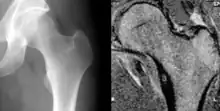

Osteoid osteoma of the lesser trochanter: X-ray and MRI with marked sclerosis around the nidus

The most common symptom is pain that can be relieved with over the counter pain medication in the beginning. After the benign tumor develops further the pain can not be alleviated with medication and minor to severe swelling starts to occur. Although, in some cases the pain level remains the same for years, and regular NSAIDs intake keeps the pain at bay. The tumor is often found through x-ray imaging. Conventional radiographs reveal a well-demarcated lytic lesion (nidus) surrounded by a distinct zone of sclerosis that allow doctors to identify the tumor.[4]

Radiographs in osteoid osteoma typically show a round lucency, containing a dense sclerotic central nidus (the characteristic lesion in this kind of tumor) surrounded by sclerotic bone. The nidus is seldom larger than 1.5 cm.

The lesion can in most cases be detected on CT scan, bone scans and angiograms. Plain radiographs are not always diagnostic. MRI adds little to the CT findings which are useful for localisation. Radionuclide scanning shows intense uptake which is useful for localisation at surgery using a hand held detector, and for confirmation that the entire lesion has been removed.[8][9]